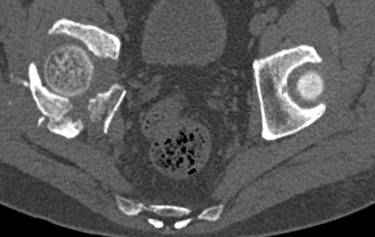

к таковым себя не причисляю, но...обычное дело для нашей страны - выкладывать 3D и не показывать стандартные проекции Judet. Дигност представляет те ракурсы, которые по-его мнению наиболее информативны, более того комп сам достраивает какие-то мелкие повреждения по 3D по своему усмотрению. По данной реконструкции можно предполагать высокий двухколонный перелом с оскольчатыми передней и задней колоннами, оскольчатую высокую переднюю колонну с задним полупоперечником или одно из перечисленных с вовлечение КПС. У меня впечатление за второй вариант, но нужно обследовать нормально - проекции, сканы.

высылаю дополнительно сканы.

По отдельным срезам и тем более по реконструкции трудно судить о сращении крыла и задней колонны с осевым скелетом.

в итоге получается прочный бублик с дыркой. При эндопротезировании в дырку помещается головка, а чашка должна неплохо заклиниться в бублике.

Главное, чтобы бублик не был разорван, что не очень понятно на представленных снимках.

Хорошо бы на рентгенограммы взглянуть и побольше срезов по своду. С каким отломком головка контактирует и как ее состояние.

Из того минимума, что представлено, мне кажется, мы имеем дело с двухколонным переломом вертлужной впадины. Обычно медиальный (центральный) "вывих" головки встречаются в сложных двухколонных переломах со смещением.